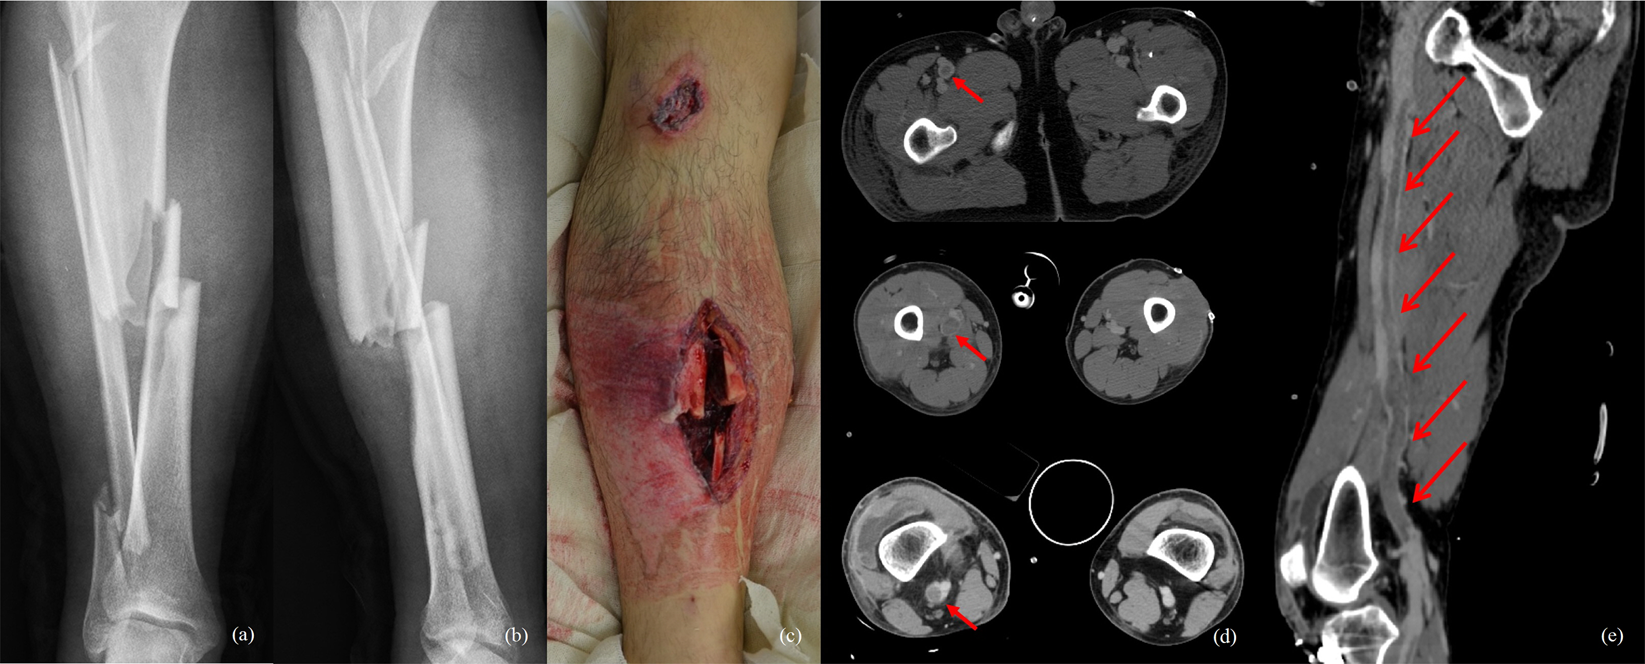

Figure 2

A 41-year-old male patient with right tibio-fibular open fracture and left ankle fracture after a motorcycle accident developed right lower-extremity severe swelling and pain during passive ankle and toe motion (a–c). CT angiography was performed. A massive thrombus in the right common femoral vein and calf were confirmed (red arrow) and chemical treatment was administered continuously (d,e).